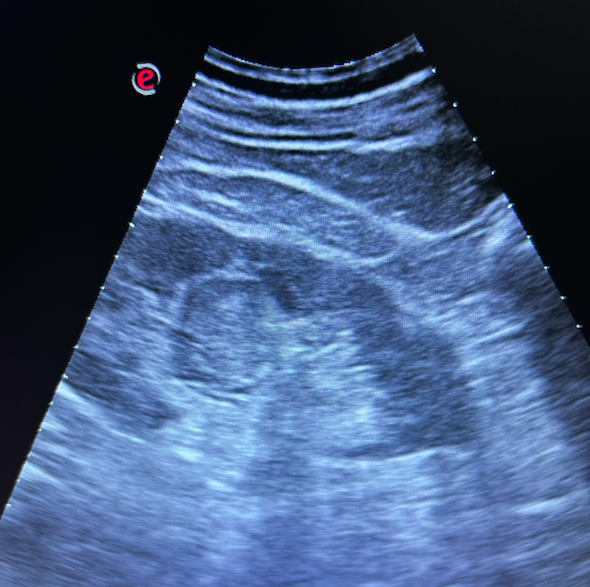

Riñones sin datos de hidronefrosis o litiasis pero en riñón izdo se visualiza lesión levemente hipoecogénica respecto a médula renal, de bordes bien definidos con doppler positivo en periferia.